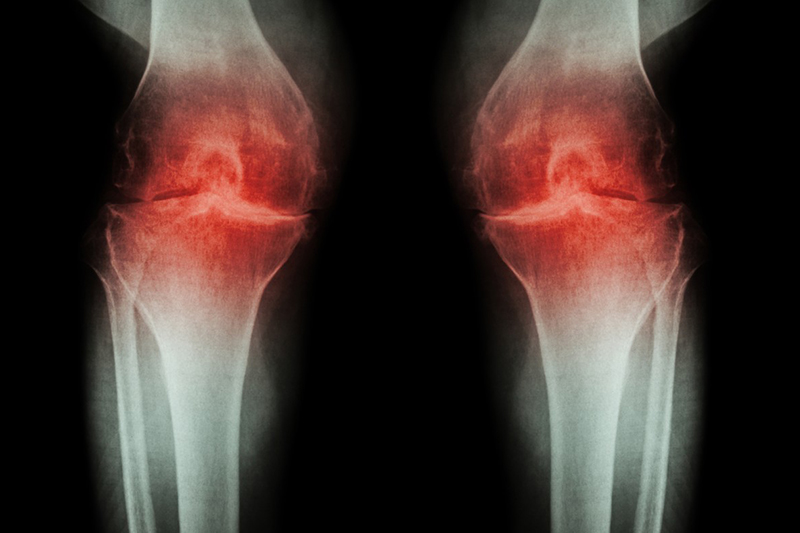

每逢「翻風落雨」,總會風濕發作?常常都聽到身邊的老人家或長輩說,每當天氣轉變,特別是雨天濕氣重,風濕就會發作,膝蓋手肘等關節位置都會隱隱作痛。到底風濕是否真的與天氣有關呢?另外還有種疾病稱作「類風濕關節炎」,與風濕又有何關係呢?

造成退化性關節炎的原因,故名思義,就是關節軟組織退化,而造成退化的原因一般為隨年齡的自然老化、關節長期受壓或磨損、曾受傷、遺傳、患糖尿病等代謝性疾病等。

回到大家最關心的問題,到底風濕(退化性關節炎)與天氣有沒有關係呢?事實上,現階段未見有研究或證明天氣會誘發退化性關節炎。而從病因及病徵來看,;都看不出天氣潮濕或下雨都與退化性關節炎或類風濕關節炎有何關係。